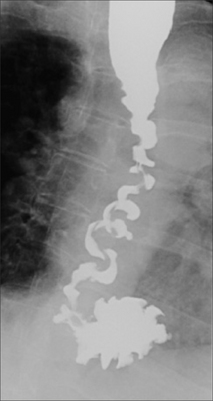

A barium swallow examination will often show the characteristic features(Fig. 27.6).

image

Figure 27.6 Female. Age 65. Recurrent episodes of chest pain. Diffuse oesophageal spasm demonstrated on a barium swallow examination. This is the so-called nutcracker oesophagus.